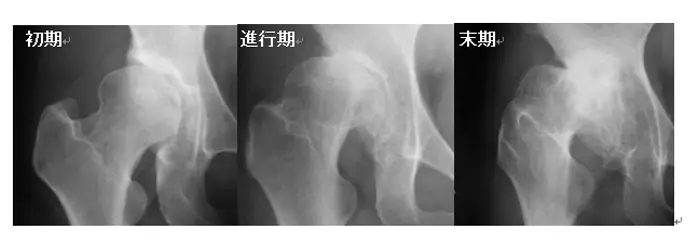

1. 変形性股関節症について

股関節疾患の代表的な疾患である変形性股関節症について説明します。変形性股関節症になる原因は、本邦では寛骨臼形成不全といって、臼蓋による大腿骨頭の被覆が少ないことが原因の場合が多く、女性に多いのも特徴です。その病期は前期、初期、進行期、末期の四段階に分類されています。前期はまだ関節裂隙の狭小などの変化がない状態で、初期は関節裂隙の部分的な狭小や骨硬化・軽度の骨棘形成がある状態、進行期は関節裂隙の部分的消失や骨嚢胞・骨棘形成がある状態、末期は関節裂隙の広範囲な消失や巨大な骨嚢胞・著しい骨棘形成がある状態です(図1)。